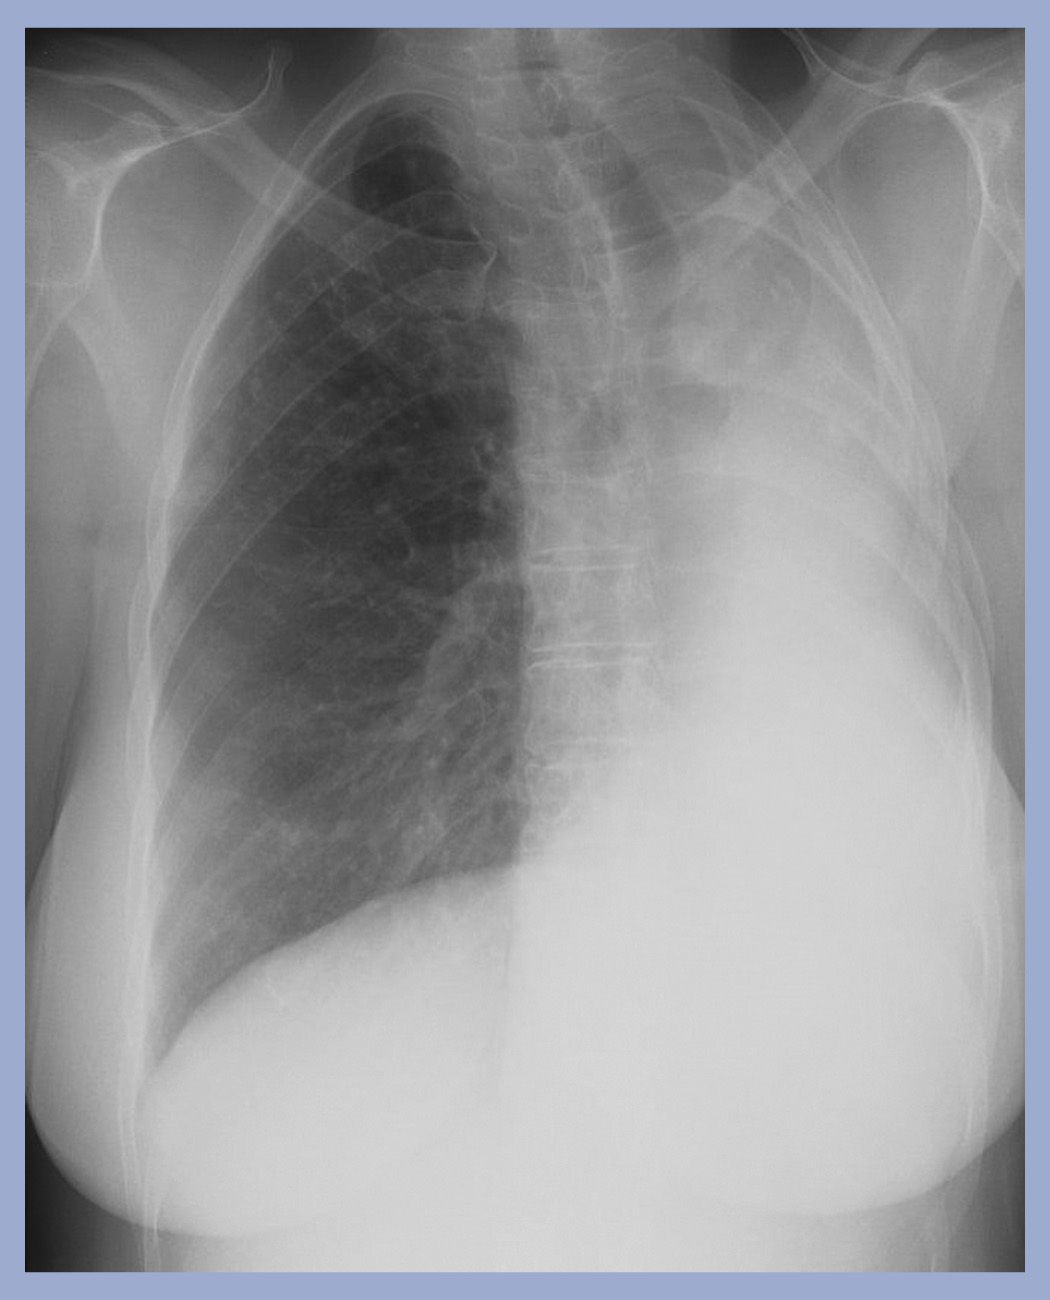

What is going on in this radiograph?

This patient had a left pneumonectomy!

The left lung is gone, and the trachea and heart have moved over to fill the void.